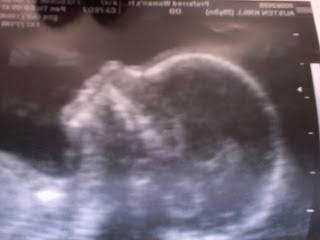

I discovered just how much I want to be a father to Peanut yesterday. We had a bit of a scare. Austen was awoken in the night by cramping, what she described as menstrual like cramping. Then again in the morning and through the early part of the morning. We were both concerned. I almost vomited my breakfast. It was at that point when I really realized just how much I love that little unborn fetus! Hell yeah! At any rate, we made a Drs. appointment immediately and they were able to see us that morning. Great news. I was stressed out the whole time. Then we had the ultrasound and all was good. Thank goodness. Thank goodness! It was relieving to hear the US tech say, everything from cervix to baby look good. It's a bit unusual to hear someone say your wife has a nice looking cervix, but whatever.. ;-)

So they also gave a sex check. It's a boy! That's now 3 out of 3 US techs that have agreed they could easily find a "3rd leg"...seriously, that's what they call it. No not a penis, a 3rd leg. It's medicine, anyhow, I digress. So it looks like Austen and I are going to be the VERY EXTREMELY OVER PROTECTIVE LOVING parents of a baby boy.

No, that imaged does not show his 3rd leg, or at least I don;t think it stretches that far... else many of us males would be quite jealous! At any rate, there he is - our beautiful lil peanut! He's the f-ing bomb! And so of course now the flurry of 1 question comes like a barrage of firepower from a line of soldiers: "Names?"